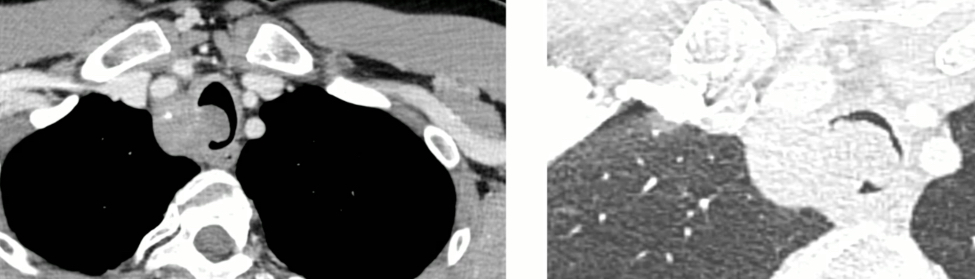

Schwannome

Schwannome

Tumeur trachéale

Tumeur trachéale

Mesures Utiles

- Distance aux cordes vocales

- Longeur de la sténose

- Distance à la carène